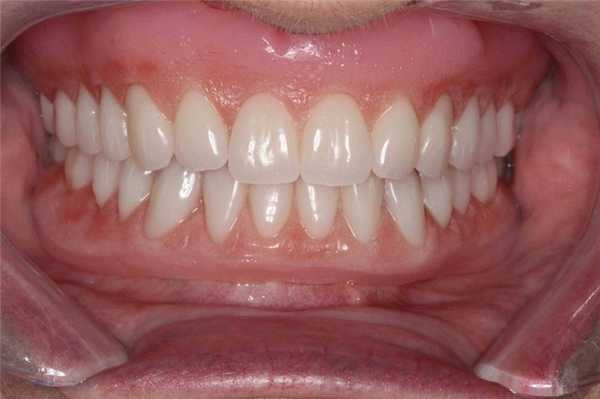

Реабилитация пациентов с полной адентией является непростой клинической задачей. Однако при реализации вышеописанного систематического подхода врачу удается добиться надлежащего восстановления функции, эстетики и фонетики в результате проведенного лечения (фото 12).

Фото 12. Вид окончательных конструкций полных съемных протезов в ротовой полости.

Данный подход также можно использовать при реабилитации пациентов съемными конструкциями на имплантатах, поскольку адаптивная способность таковых несколько ниже, чем обычных съемных протезов, учитывая стабильность установленных внутрикостных опор.